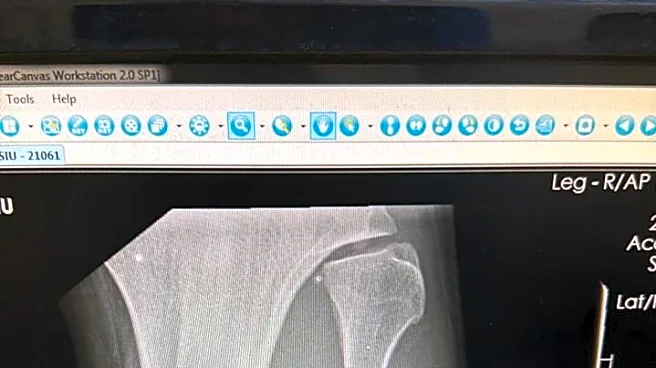

And he did it with a broken leg, snapping his fibula via Sutherland leg kick in the opening frame.